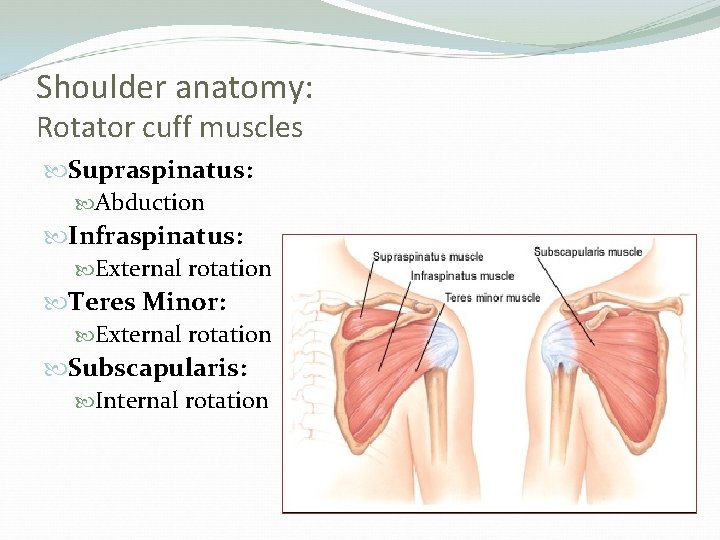

Shoulder Anatomy: Rotator Cuff Muscles Depress humeral head against glenoid

Shoulder anatomy: Rotator cuff muscles Supraspinatus: Abduction Infraspinatus: External rotation Teres Minor: External rotation Subscapularis: Internal rotation